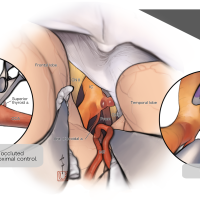

術後イラストシリーズ